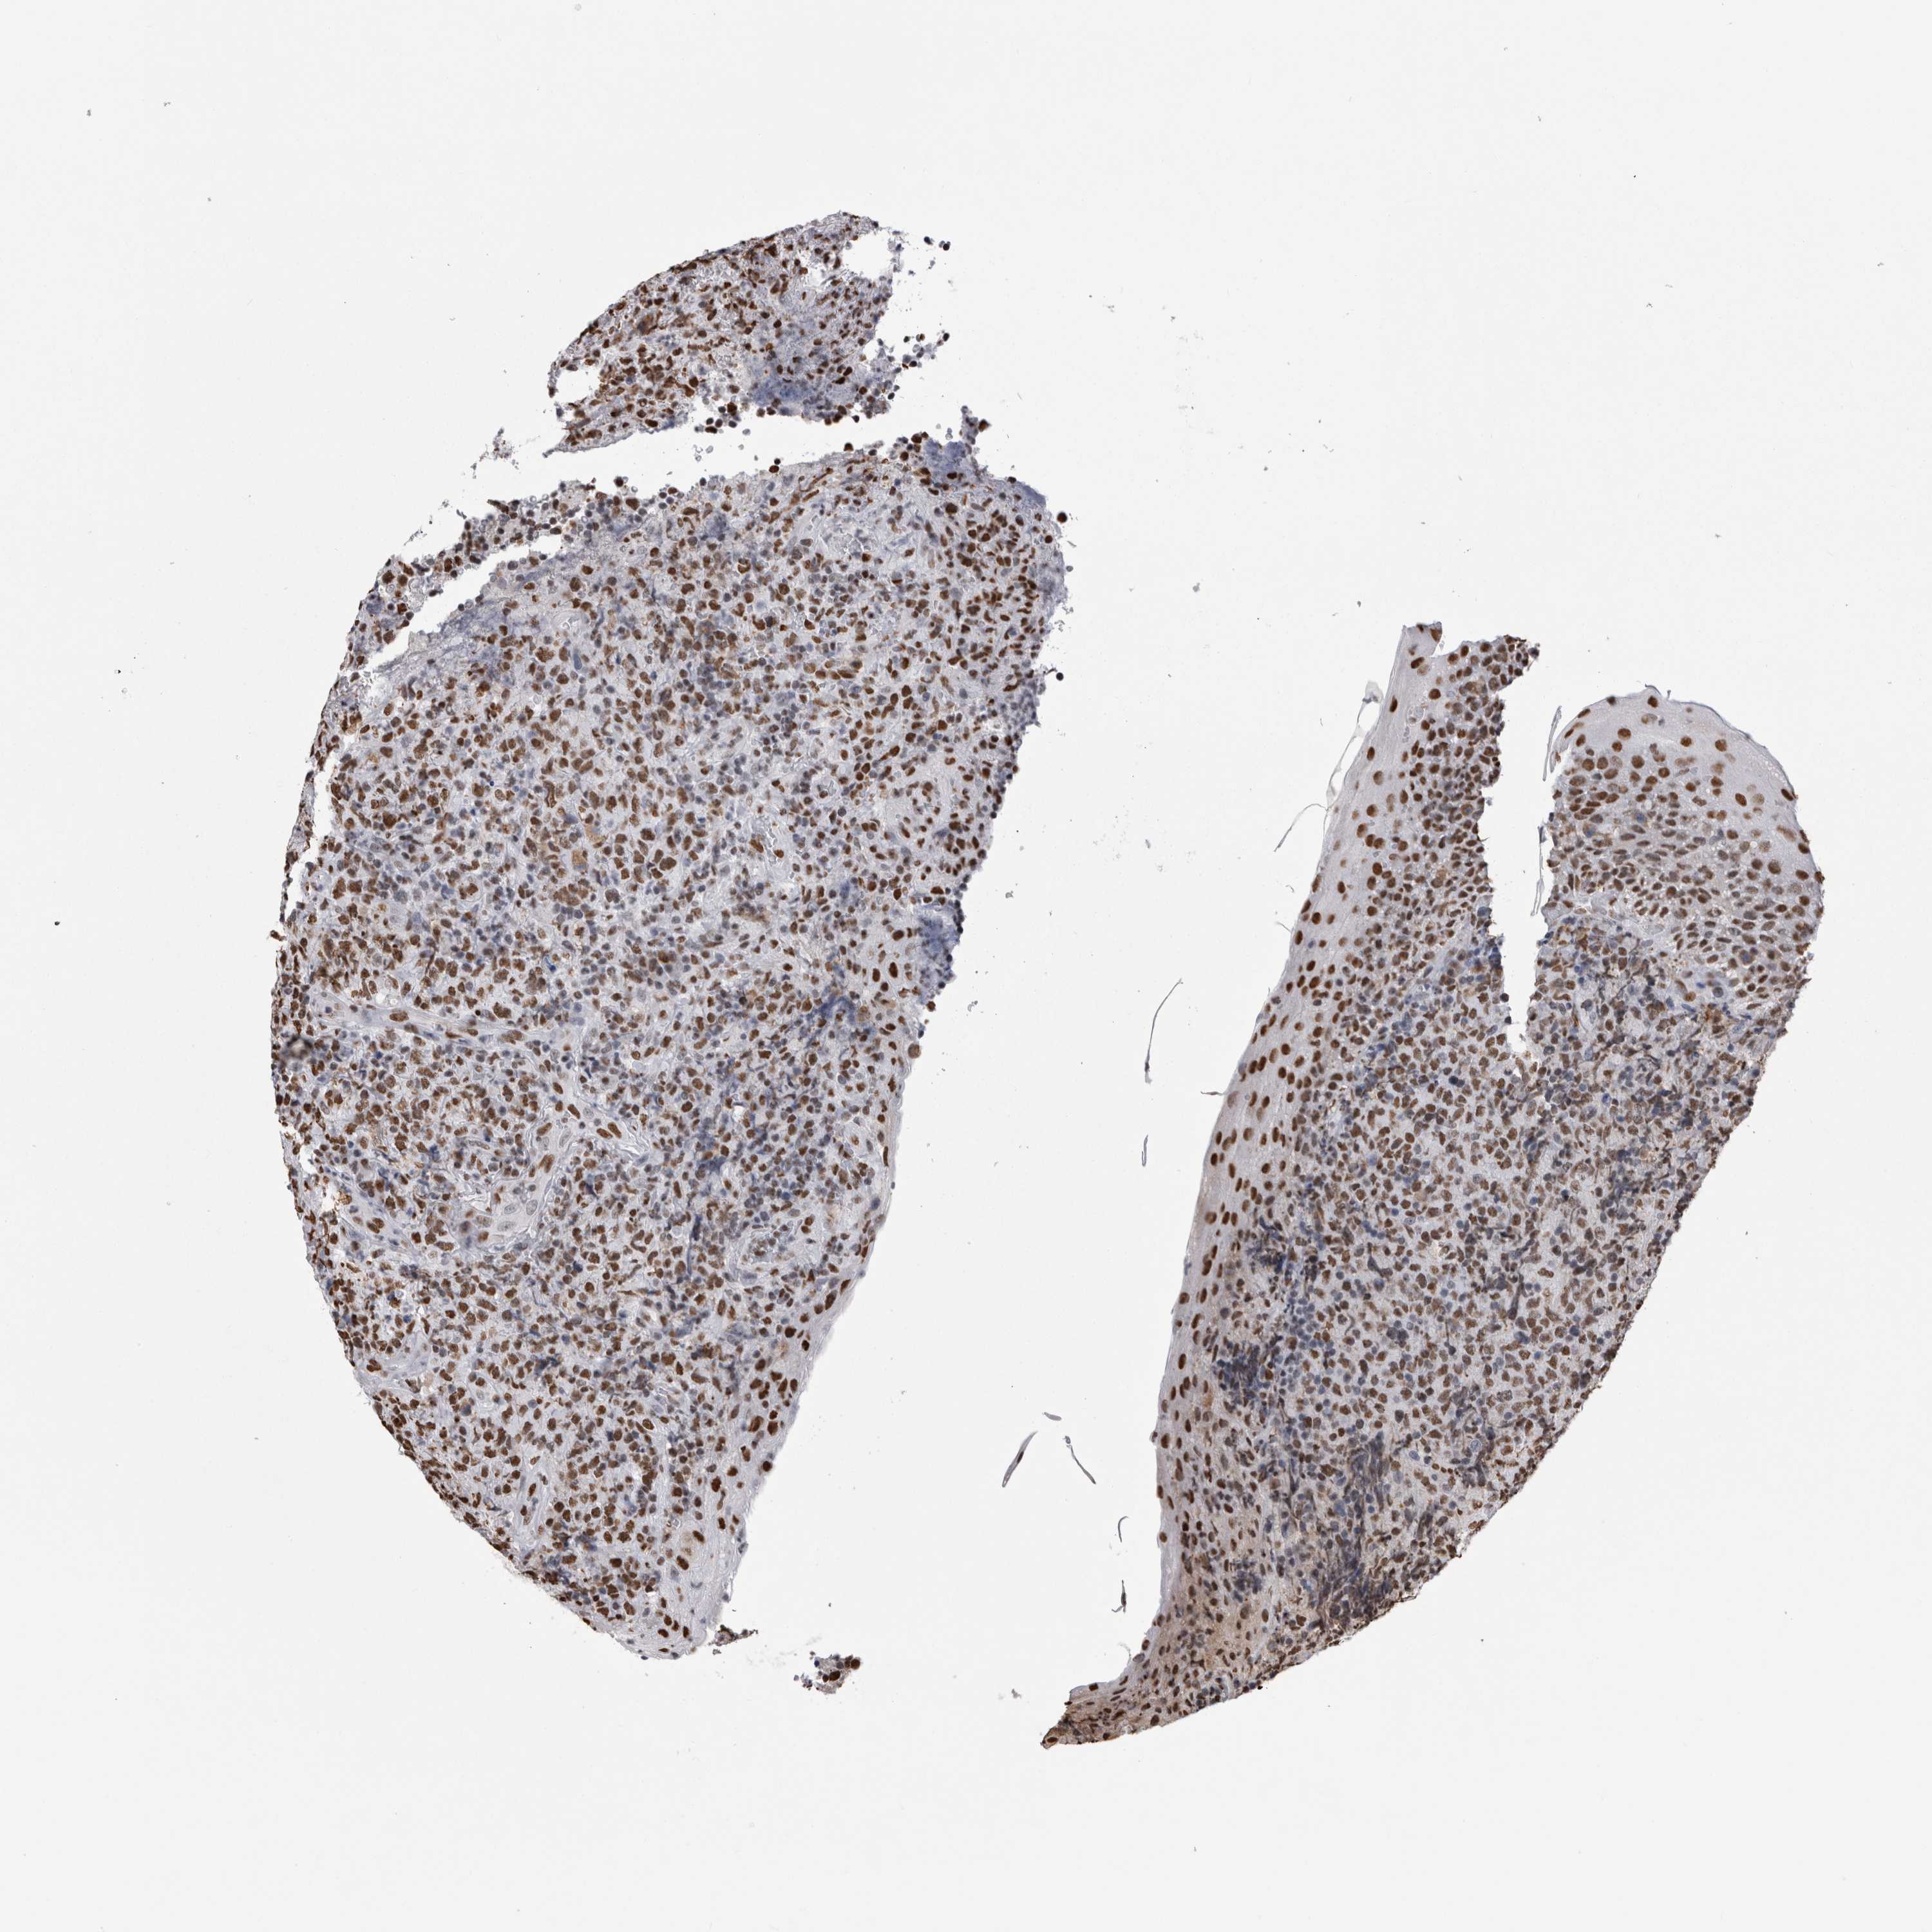

CANCER LYMPHOMA Show tissue menu

LYMPHOMA - Protein expressioni

A mouse-over function shows sample information and annotation data. Click on an image to view it in a full screen mode. Samples can be filtered based on level of antibody staining by selecting one or several of the following categories: high, medium, low and not detected. The assay and annotation is described here.

Antibody HPA026558

Staining

High

Intensity

Strong

Quantity

>75%

Location

Nuclear

Hodgkin's disease, NOS

Malignant lymphoma, non-Hodgkin's type, High grade

Malignant lymphoma, non-Hodgkin's type, Low grade